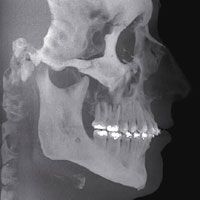

Neuste 3D-Röntgentechnik mit dem digitalen Volumentomograph ("Kopf-CT")

Dies bietet phantastische 3D-Einblicke in versteckte Regionen und ermöglicht Untersuchungen aus anderen Blickwinkeln. So kann z.B. am Computer jeder Eingriff geplant und die 3D-Ansicht des Kiefers in jeder beliebigen Ebene rekonstruiert werden.

Bilder höchster Qualität für exakten Durchblick und genaues Arbeiten

Details wie Knochen, Schmelz, Dentin, Parodontalspalt usw. werden besser dargestellt als in jedem anderen Verfahren.